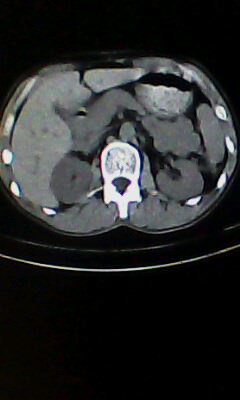

胰尾部占位?

未见明显异常。“胰尾占位”为肠管

口服造影剂是必须的